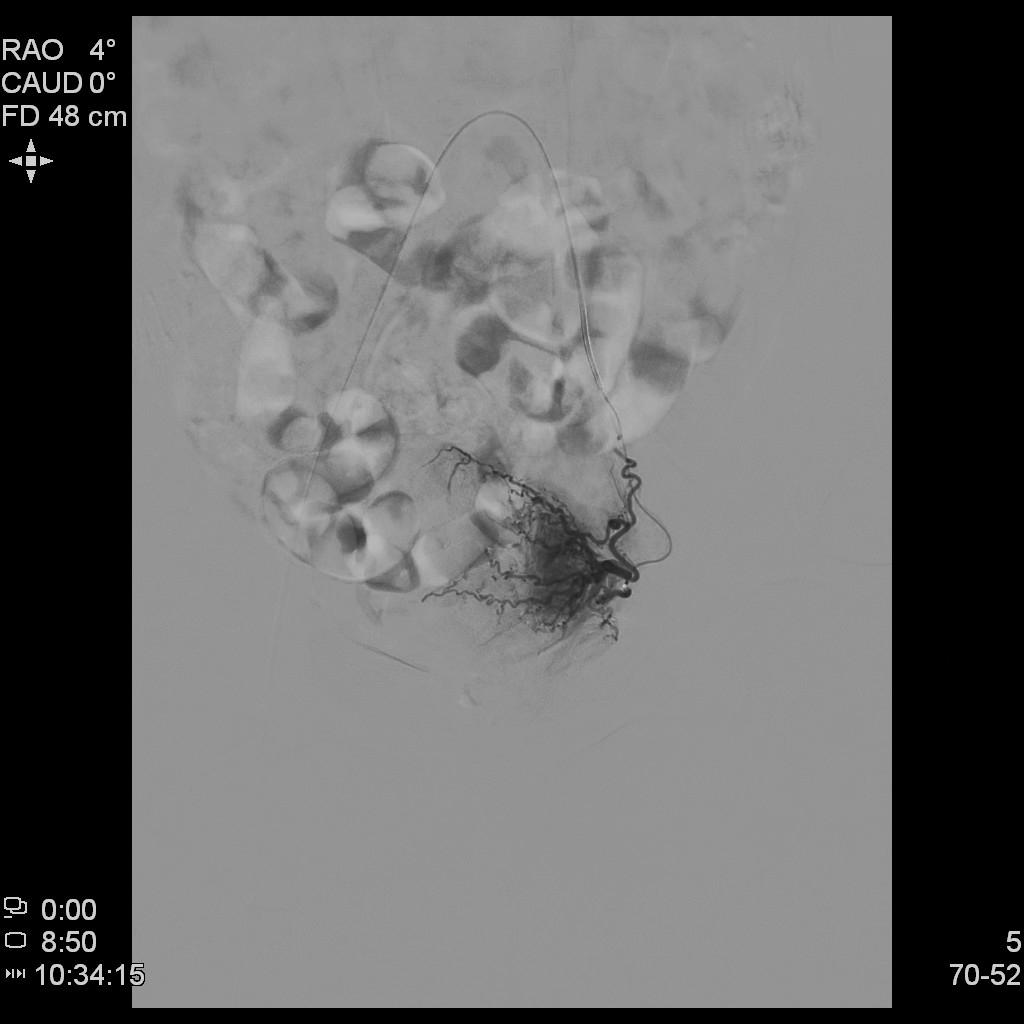

- 经左侧桡动脉穿刺置管,行腹主动脉造影显示双侧子宫动脉增粗、迂曲。

- 超选择插管右侧子宫动脉病灶供血动脉造影+栓塞治疗。

- 超选择插管左侧子宫动脉病灶供血动脉造影+栓塞治疗。